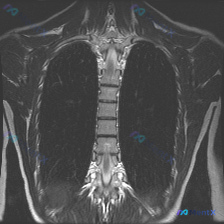

整理到一份临床诉求指向「脊柱侧弯」的病例资料: 仅有的影像检查是胸部MRI冠状位T2加权像,影像报告的核心发现是: - 双侧肺野、纵隔、心影未见明显局灶性病变或占位; - 胸椎序列清晰,椎体形态基本正常,未见明显的形态异常或骨质信号改变; - 双侧胸廓、软组织结构大致对称。 但结合「脊柱侧弯」的核心...

整理了一份影像分析资料,觉得这个矛盾点挺有意思的,拿出来和大家讨论。 资料背景是:一张胸部MRI T2加权像(冠状位),临床核心诉求是排查脊柱侧弯。 先放几个关键的影像所见: - 肺实质、纵隔、胸膜腔、胸壁软组织都未见明显异常信号或占位 - 报告写了“胸椎椎体及附件形态基本完整”、“脊柱旁软组织未见...